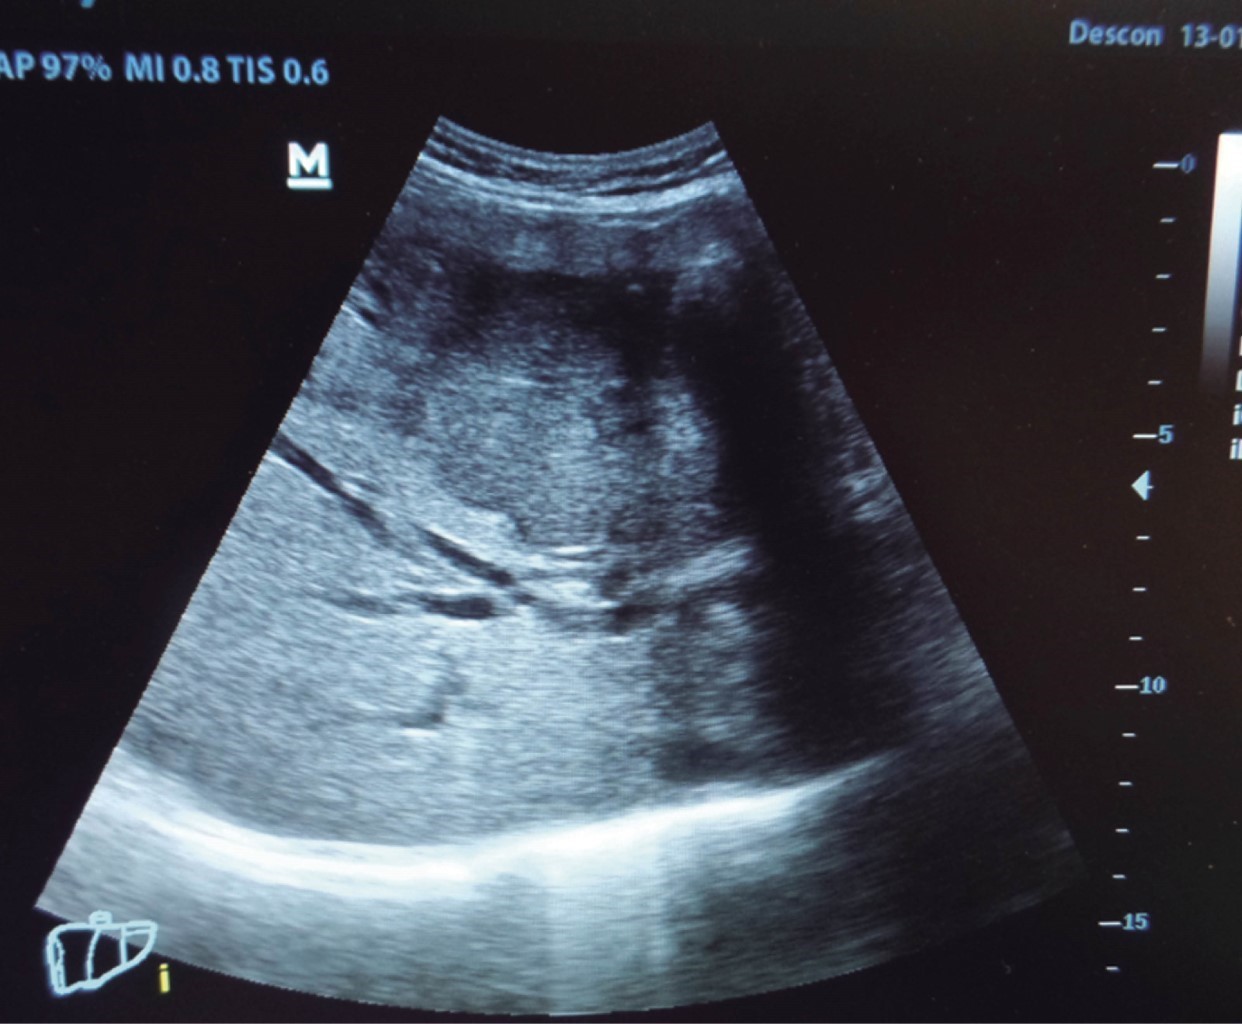

El cirujano general aborda particularmente problemas clínicos que incluyen el aparato digestivo, el cuello, la pared abdominal y los trastornos del sistema circulatorio y el tórax. Un artículo publicado en 2008, por Lindelius,15 demostró que la implementación del ultrasonido por parte del cirujano general en casos de dolor abdominal agudo incrementó en 7.9% la precisión diagnóstica. En la consulta cotidiana de la especialidad, incorporar el rastreo sonográfico al área explorada agrega minutos al examen clínico que aportan datos de notable valor por la objetividad y precisión. El abdomen suele ser el sitio que los cirujanos generales exploramos con más frecuencia. Es posible en una consulta cotidiana hacer todo el protocolo de ultrasonido de abdomen superior en minutos, que incluye ambos cuadrantes superiores y los flancos, pudiendo observar el hígado, la vesícula y los conductos biliares, ambos riñones, el bazo, parte del páncreas y, con ayuda del Doppler color, los principales vasos de la región como la vena cava inferior, la aorta abdominal, la vena porta, los vasos esplénicos y la arteria hepática. Puede haber limitantes como el contenido gástrico, el nivel de llenado de la vesícula biliar o la constitución del paciente y su capacidad de cooperar con el estudio. Pero con la práctica cotidiana, se adquieren las destrezas y el refinamiento suficientes para lograr, con la experiencia acumulada, producir imágenes de relevancia diagnostica inmediata. En la fase de entrenamiento, contrastar nuestros hallazgos con información disponible en la red, con los colegas imagenólogos, o cirujanos ya experimentados en ecografía, permitirá la retroalimentación y la tutoría esenciales de toda curva de aprendizaje. Tradicionalmente se consideraba que aquellos órganos que contienen una mezcla de líquido y gas (intestino, estómago) no son valorables por ultrasonido, el gas produce un efecto rarefacción, ya que no comprime las ondas como un tejido solido o un medio líquido, la señales entonces se dispersan impidiendo que regresen como ecos y permitan al procesador formar una imagen congruente con el órgano explorado. Sin embargo, cuando esta condición cambia como consecuencia de un estado patológico, es posible identificar el contenido intestinal o el gástrico y darnos una idea más aproximada de lo que realmente está ocurriendo en ese abdomen. Podemos, por ejemplo, saber si un estómago está lleno de líquido, o si el intestino contiene residuo sólido, líquido o gaseoso. Los equipos actuales pueden incluso ver en detalle la pared intestinal cuando ésta esté dilatada. Se puede distinguir cuando el colon está ocupado de líquido a nivel del flanco izquierdo como podría ser en una colitis amebiana o en una oclusión intestinal,16 donde se observa dilatación del intestino delgado ≥ 25 mm, el peristaltismo anormal, la presencia de líquido libre intraperitoneal y el edema de la pared intestinal (Figura 2). En casos de dolor abdominal agudo, el ultrasonido puede, en forma inmediata, permitir diagnósticos diferenciales como el hallazgo de una dilatación pielocalicial por nefrolitiasis (Figura 3), o un aneurisma de la aorta abdominal (Figura 4). Un estudio prospectivo realizado en Irvine, California,17 encontró que la a capacidad diagnóstica del médico de primer contacto practicando el ultrasonido para detectar una colelitiasis tiene una especificidad de 87% y una sensibilidad de 82%, mientras que la prueba de ultrasonografía realizada por radiología tuvo sensibilidad de 83% y una especificidad de 86%. Es decir, que, ahorrando tiempo al paciente, el diagnóstico de colelitiasis es factible agregando unos minutos al examen físico inicial. En casos de apendicitis, el método diagnostico considerado como el estándar de oro es la tomografía axial computarizada (TAC). Sin embargo, tiene inconvenientes como su disponibilidad, su costo, el riesgo de radiación en niños y pacientes embarazadas. En tales situaciones, sobre todo en niños, sexo femenino o pacientes delgados, el ultrasonido es una poderosa herramienta que complementa el examen clínico inicial. Las ventajas del ultrasonido frente a la tomografía serian su ubicuidad (ya está en la sala de emergencias), el bajo costo, la ausencia de radiación y el diagnóstico diferencial con causas ginecológicas o genitourinarias de dolor. En apendicitis, la sensibilidad y especificidad de la TAC es de 99.4% y 80.0%, respectivamente. Para el ultrasonido, la sensibilidad diagnóstica es de 83% y la especificidad de 90%. La tasa de apendicectomía negativa es ligeramente mayor en el grupo de TAC que en el del ultrasonido, es decir, 7.1% (3/42) (TAC) en comparación con 4.67% (5/107) (ultrasonido). Hay que recalcar que el ultrasonido es operador dependiente. La experiencia y la calidad del equipo juegan un papel importante.18 La apendicitis tiene varios hallazgos característicos, como la pared edematosa y el aumento de grosor general. Se toman para criterios de positividad una estructura tubular aperistáltica no compresible que mide más de 6 mm de diámetro en el cuadrante inferior derecho (Figura 5).19-21

Figura 3